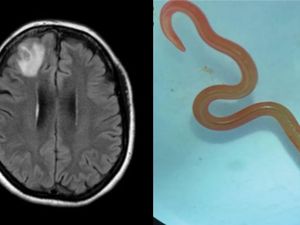

Ngeri, Dokter Temukan Cacing Parasit Ular Piton 8 Cm di Otak Wanita Australia

Dokter menemukan cacing parasit sepanjang 8 cm di dalam otak wanita berusia 64 tahun. Hal ini menyebabkan kerusakan serius dan gangguan ingatan.